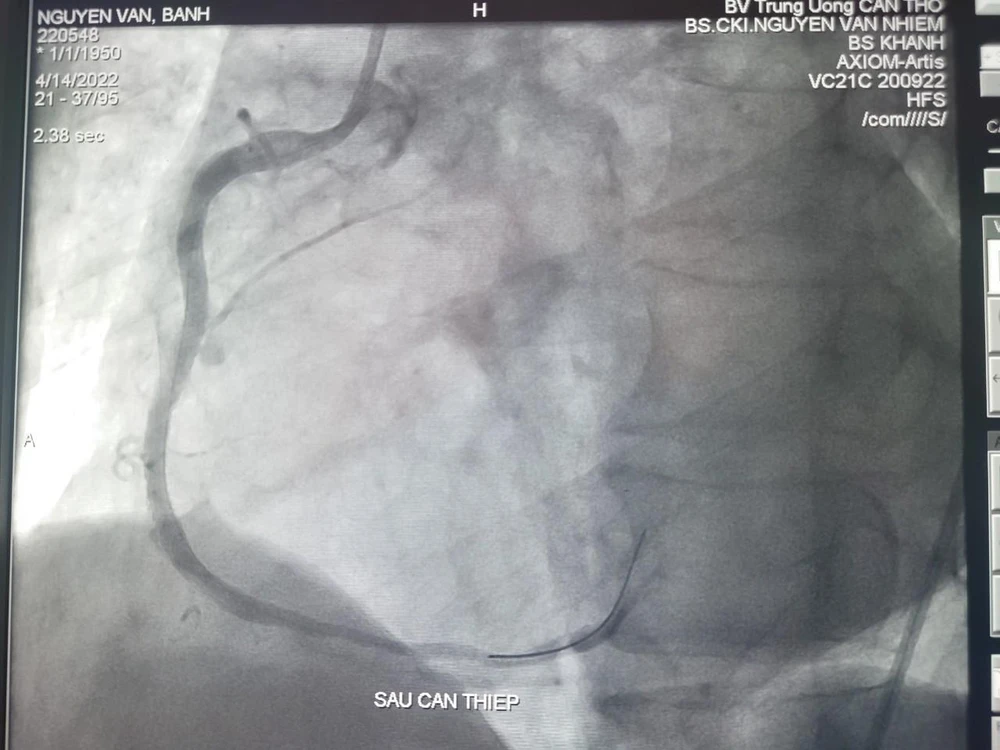

Hình ảnh DSA mạch trước và vành sau can thiệp. Ảnh: BVCC

Tiếp đó, ê kíp chụp và can thiệp mạch vành cấp cứu, kết quả ghi nhận bệnh nhân tắc hoàn toàn RCAII (động mạch vành phải đoạn giữa) và huyết khối. Các bác sĩ đã can thiệp thành công sang thương bằng stent phủ thuốc, kết quả tái thông hoàn toàn mạch vành sau can thiệp sau 20 phút.